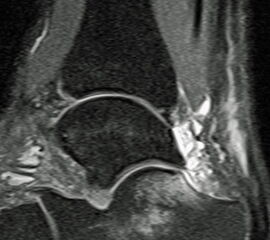

• MRT zur Beurteilung der Achillessehnendegeneration und zur Bestimmung der Defektstrecke (Abbildung 1).